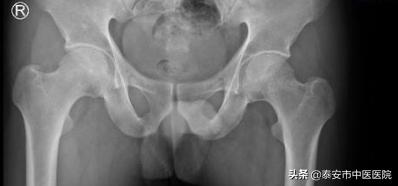

主治医生王乃舜介绍到,该患者双髋部疼痛活动受限4月余,有长期饮酒史,吸烟史,术前做了相关检查示双侧股骨头缺血性坏死(II期),考虑患者年龄偏高,保守治疗效果不佳,症状以疼痛活动受限为主,选择微创髓芯减压加支撑棒植入术对髋关节结构影响很小,最大限度减少病人的手术损伤,改善症状,延缓疾病进展,临床疗效十分满意。

术前诊断